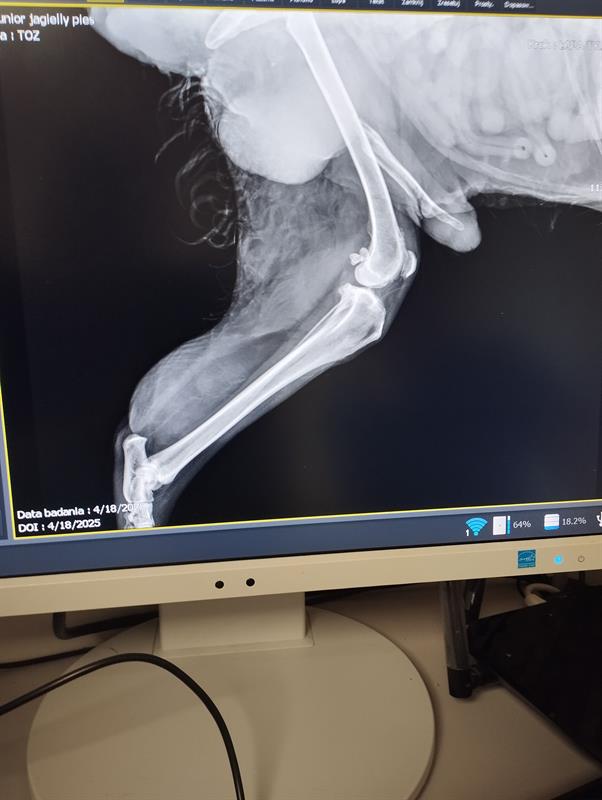

Pies leżał tuż przy drzwiach. Na podłodze. Miski z wodą i jedzeniem stały opodal. Ale on nie był w stanie się podnieść. Nie miał dość siły, żeby stać. Fot. Towarzystwo Opieki nad Zwierzętami

Leżał na podłodze. Przy pełnych miskach. I nie był w stanie się podnieść z własnych odchodów. Odór gnijącego mięsa - jego nabrzmiałego i ropiejącego guza przy zadzie - czuć było już na półpiętrze, tuż przed mieszkaniem, w którym… w potwornym bólu otwartych ran, odparzeń i odleżyn dogorywał, bez pomocy, miesiącami. Pies Junior.